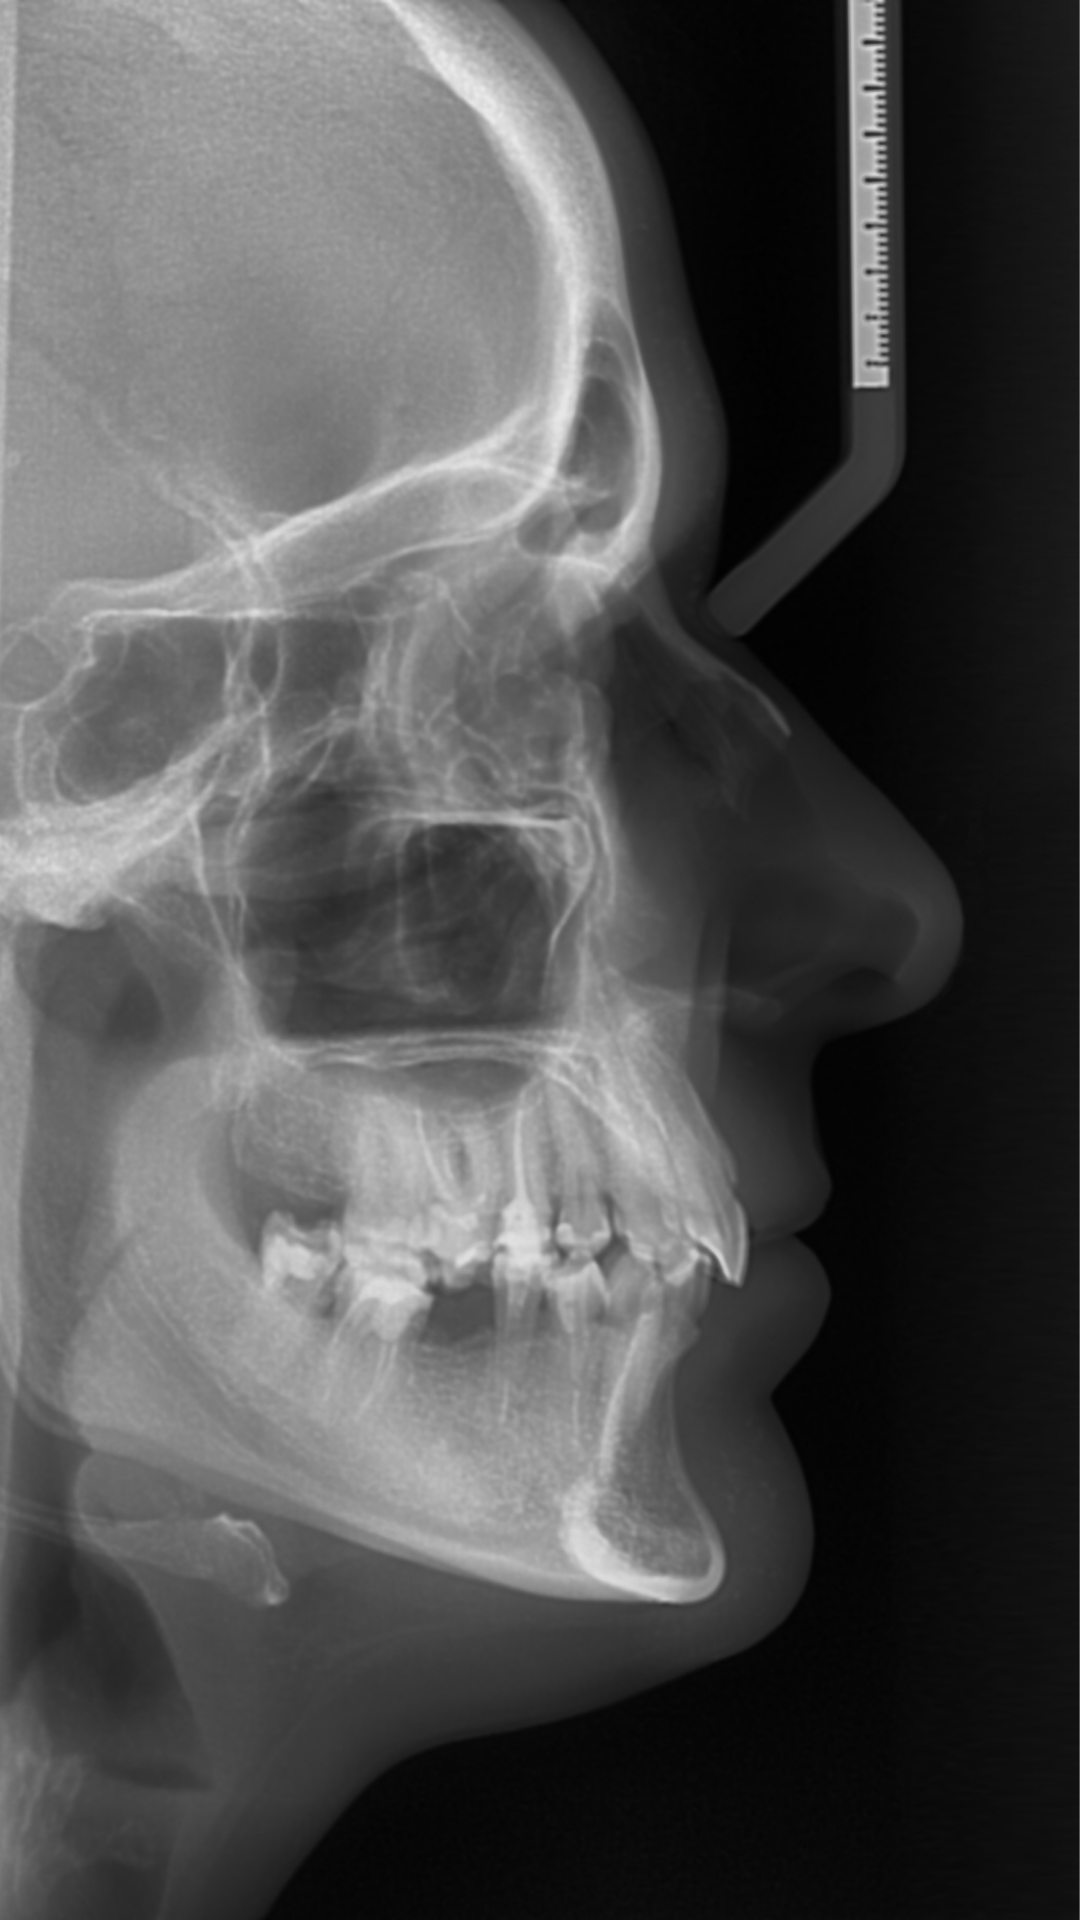

¿Planeas un tratamiento de ortodoncia? Nuestros análisis ortodónticos 2D incluyen cefalometrías, modelos digitales y fotografías estandarizadas.